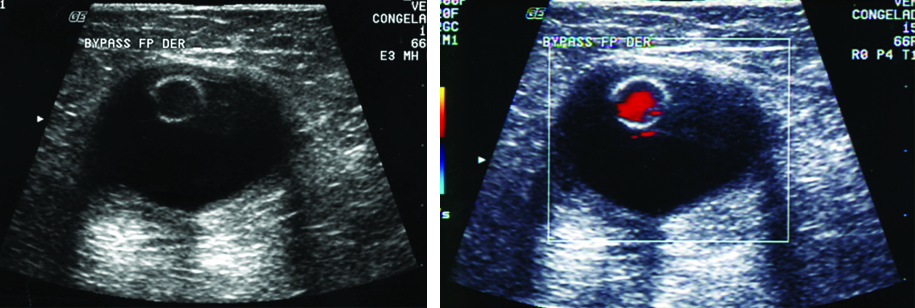

IMÁGENES POSTQUIRÚRGICAS

Realizado el diagnóstico de la arteriopatía, nivel de estenosis y grado de colateralización, el cirujano planteará la cirugía. Es importante para el médico radiólogo saber el tipo de cirugía realizada y el tiempo de evolución de la misma para una correcta interpretación de las imágenes.

De no contar con información sobre el tipo de cirugía realizada, el médico radiólogo llevará a cabo una anamnesis al paciente sobre el tema y la sintomatología actual; asimismo lo examinará en búsqueda de cicatrices que le permitan reconocer la técnica empleada. Luego procederá a evaluar el tipo de injerto y la topografía del bypass, realizará la medición de las velocidades de flujo en las anastomosis y en el injerto, y procederá a medir el índice tobillo-braquial. Identificará el tipo de bypass femoral. Durante el examen se evaluará la velocidad de pico sistólico en el sector de las anastomosis y en el injerto. En el período postquirúrgico el flujo típico es de hiperemia, con diástoles prominentes. Al cabo de dos meses se establece un patrón trifásico típico. La velocidad en el bypass debe ser superior a 40 cm/seg (Fig. 21).

Complicaciones de los bypass

En estadios precoces se pueden observar bajas velocidades sanguíneas debido a un flujo de entrada o salida insuficiente, por fallas en la anastomosis por problemas intrínsecos del injerto. Los hematomas peri-protésicos son complicaciones frecuentes en el período quirúrgico inmediato (Fig. 23). Dentro del primer año se pueden dar obstrucciones por defectos en la cirugía o por hiperplasia fibrointimal. Luego de los dos años puede darse la progresión de la enfermedad en los vasos nativos proximales y distales al bypass. La complicación más tardía, de 5 a 10 años, es el desarrollo de pseudo-aneurismas en el lugar de las anastomosis distales.